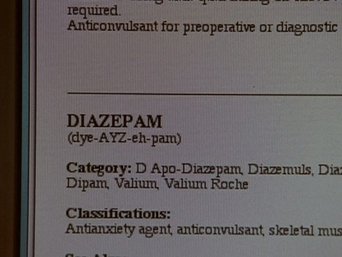

In a special black and white episode patterned after The Twilight Zone, a mysterious customer offers Felicity advice on how to ease her constant heartache. Felicity visits a clinic, where she soon learns that the doctors use horrific methods to mend a broken heart. Felicity and her friends end up trapped in a small, bare room from which there is no escape. The contents of Meghan's box are revealed (for the purpose of this episode only).